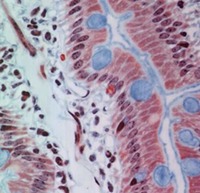

Paneth cells and Enteroendocrine cells

The muscularis mucosae is well developed and can be seen at the base of the villi.

It follows the folds of the Plicae circulares. Look at the base of the

glands, the Crypts. You can see clearly the granulated PANETH CELLS distinguished by

red granules pointed towards the lumen of the gland. You may also see

ENTEROENDOCRINE cells at the base of the glands. Examples of both types of cells are seen

in the following photo. Recall that the red granules of the enteroendocrine cells are

pointed towards the blood vessels in the lamina propria.